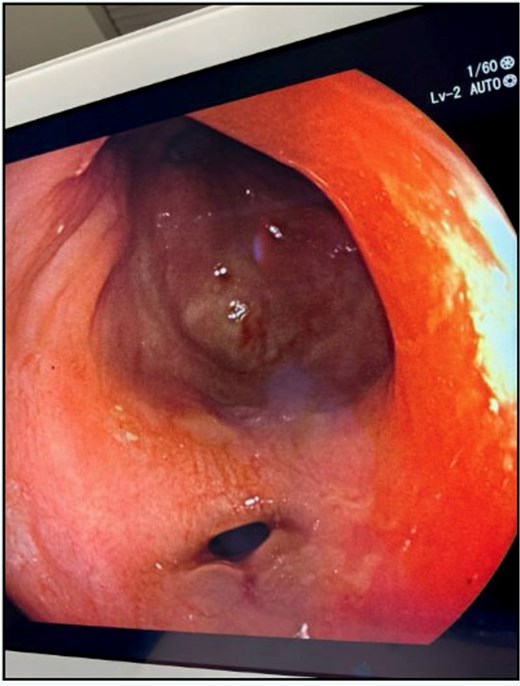

Examination under anesthesia with flexible sigmoidoscopy revealed a right lateral rectal wall disruption approximately 8 cm from the anal verge, involving close to 30% of the rectal circumference (Fig. 2). In the absence of peritonitis, the patient was admitted for observation and managed nonoperatively with bowel rest and intravenous ceftriaxone 1 g every 24 h, and metronidazole 500 mg every 12 h.

Initial findings on exam under anesthesia with flexible sigmoidoscopy revealing right lateral rectal wall disruption 8 cm from the anal verge, involving ~30% of the luminal circumference.